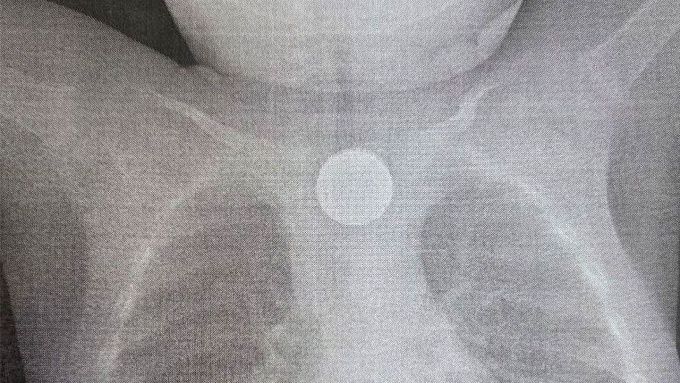

фото: ДРКБ

Годовалого малыша, который проглотил монету и батарейку, спасли от смерти. Инородные тела вызвали ожог третьей степени, рассказали в ДРКБ.

В Улан-Удэ врачи оперативно удалили 2-рублевую монету и дисковую литиевую батарейку из пищевода при помощи внутрипросветной эндоскопии. Батарейка вызвала химический ожог 3 степени, что представляло серьезную угрозу для жизни.